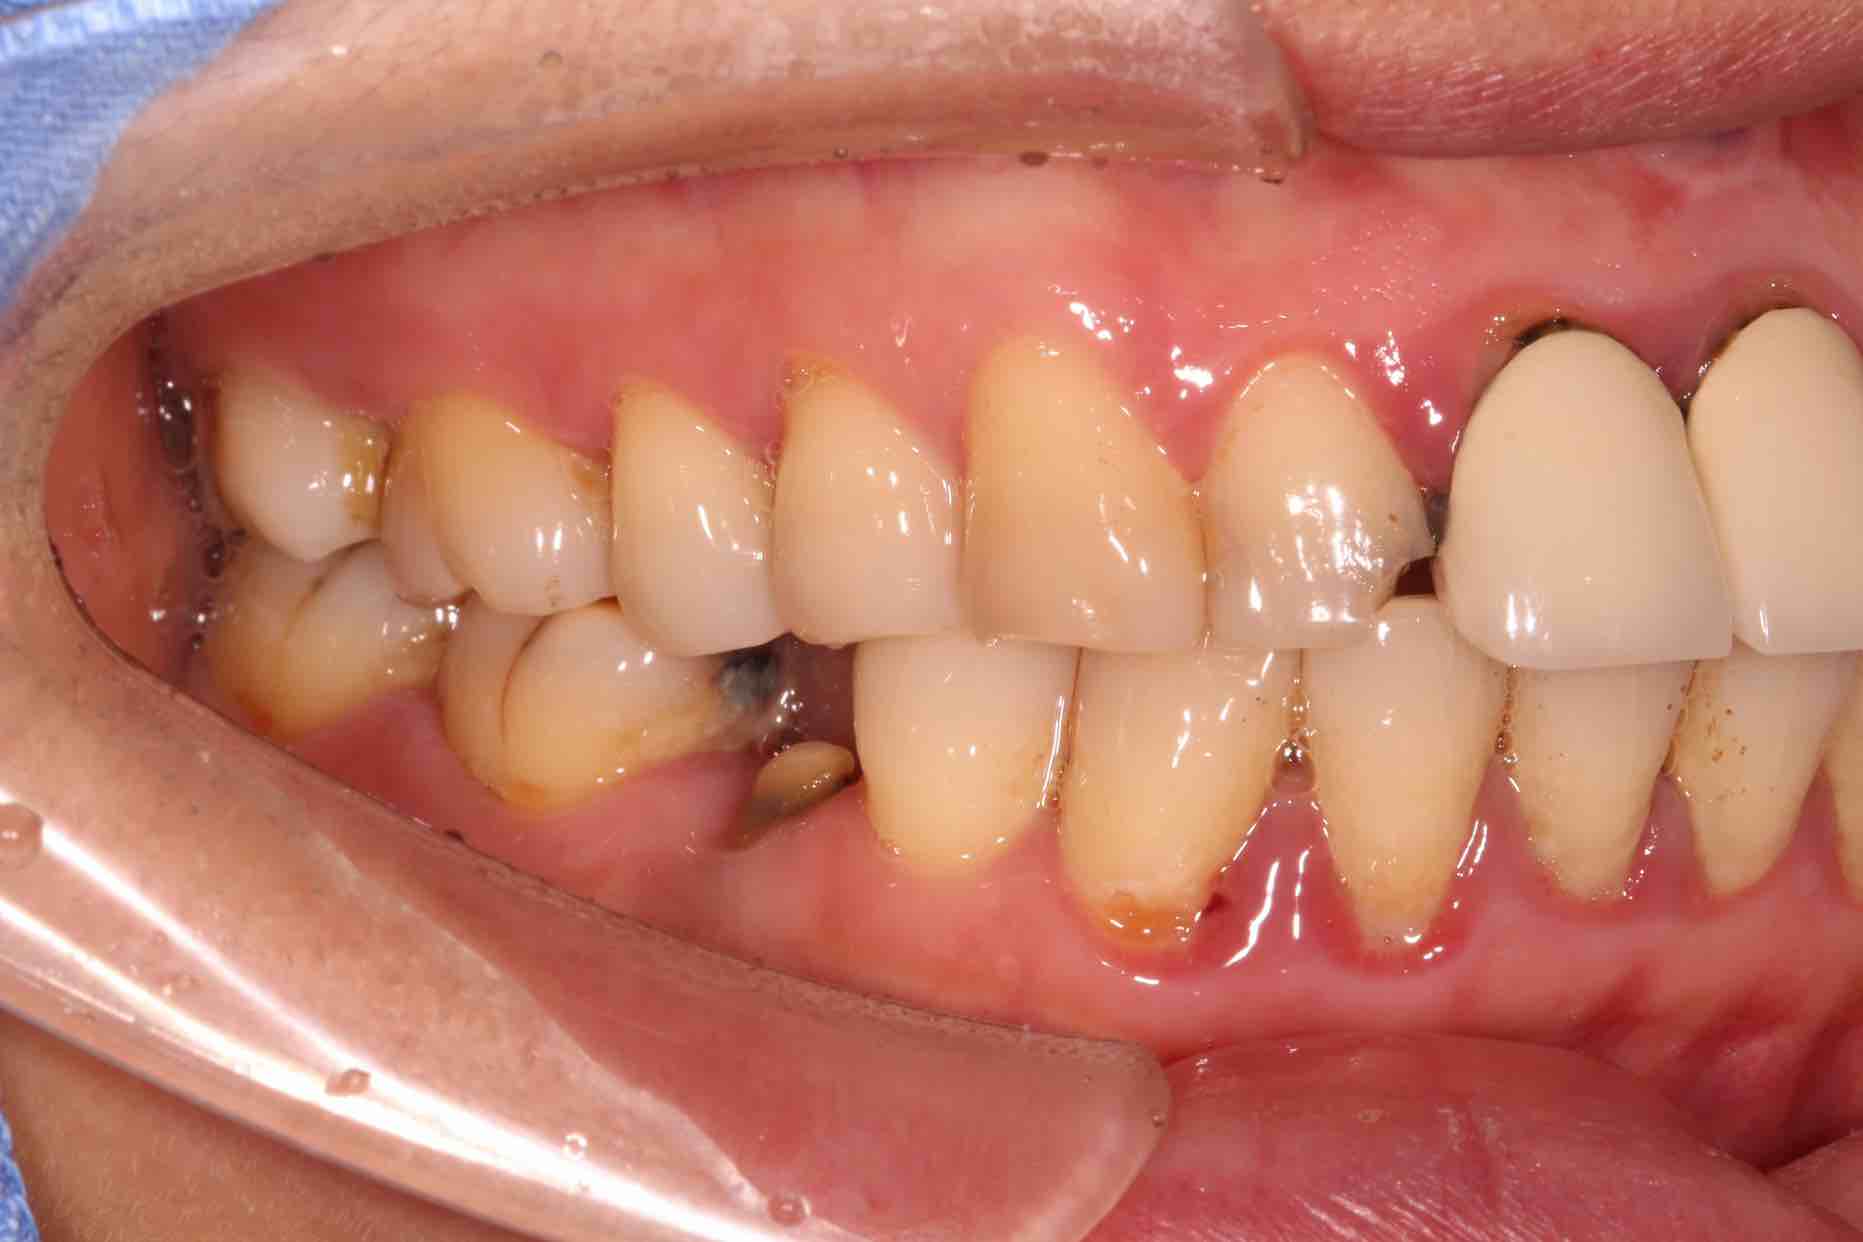

患者中年女性,11、21外院制作烤瓷冠,冠边缘不密合,牙龈退缩发黑,龈缘红肿,颜色不美观且X线检查21根管治疗不完善,由于牙冠不密合,11严重龋坏已有牙髓炎症状,我们对11进行了根管治疗,21进行了根管再治疗,最后CEREC扫描修复。